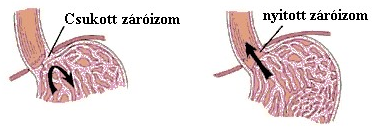

• A húgyhólyag krónikus, fájdalommal járó gyulladása és kezelése

• Reflux

• Reflux 2

• Reflux 3 - Válasz 32

• Reflux oka, gyógyszeres és alternativ kezelése. Laparoszkópos és TIF műtéti eljárás - Válasz 55

• Reflux gyermekkorban. Máj és epehólyag tisztítás. - Válasz 23

• Reflux okai - Válasz 17

• Refluxra szedett protonpumpa gátlók (PPI) kedvezőtlen hatásai - Válasz 80